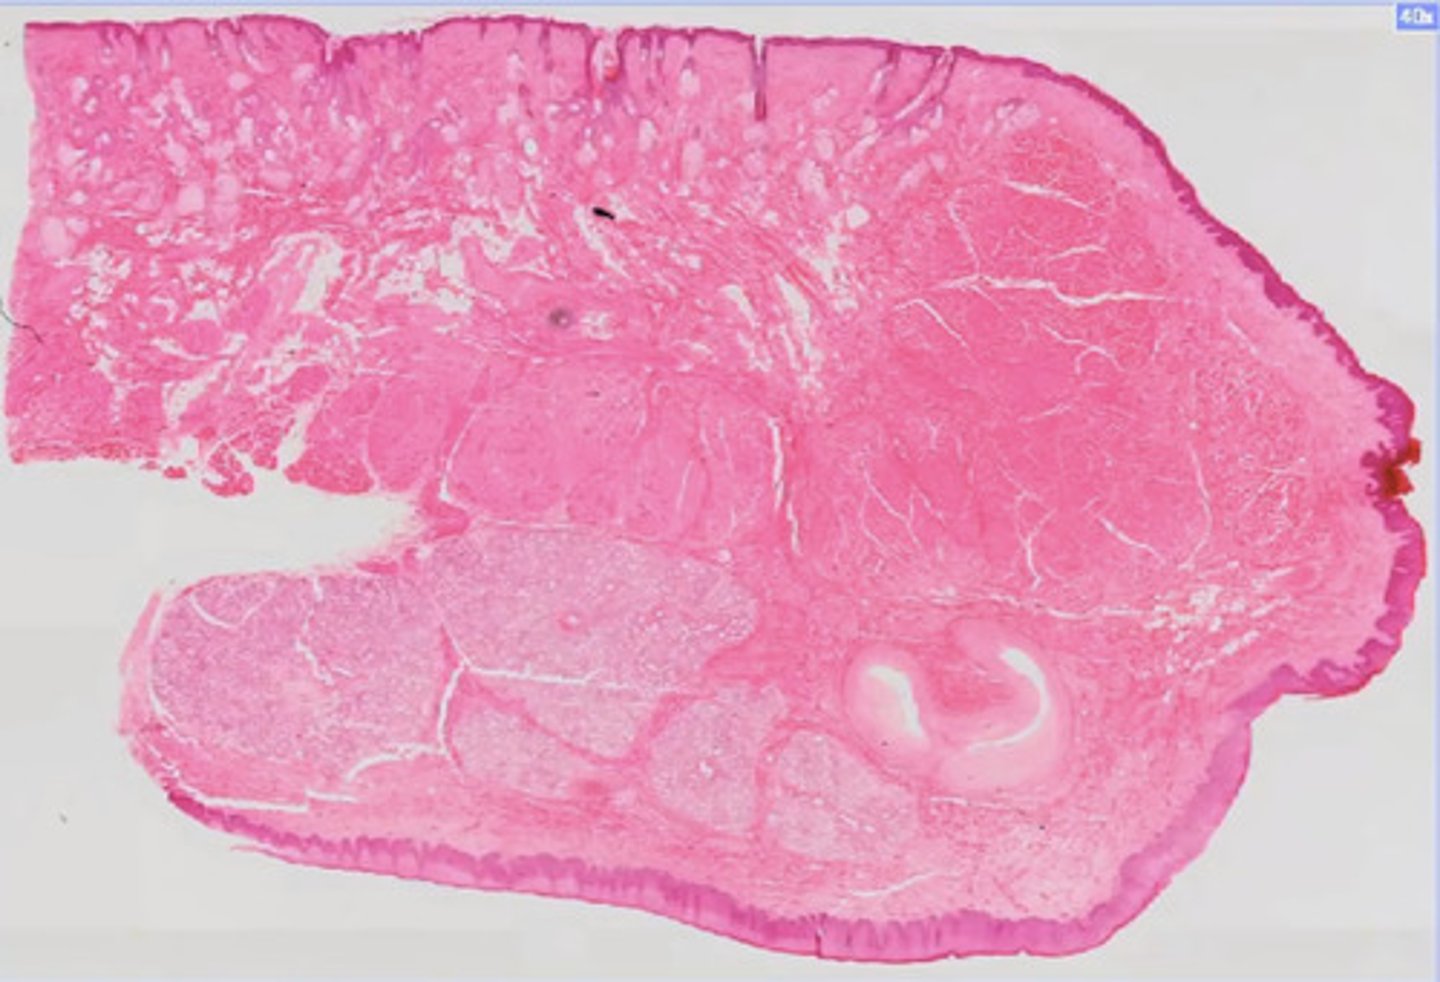

Skóra nieowłosiona (H+E)